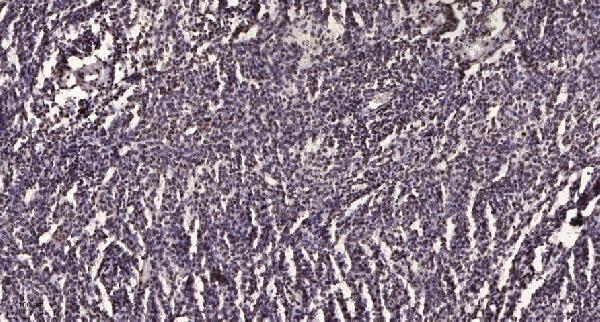

Immunohistochemical analysis of paraffin-embedded human brain tumor. 1, Antibody was diluted at 1:200 (4° overnight). 2, Tris-EDTA, pH9.0 was used for antigen retrieval. 3, Secondary antibody was diluted at 1:200 (room temperature, 45min).